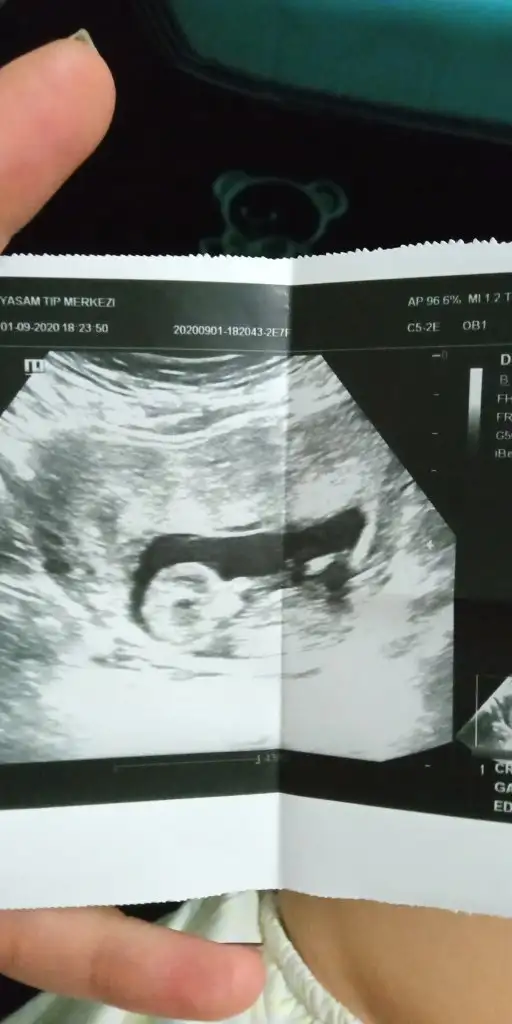

Erkek diyecem emin olamadım net değil nubu 12-13 haftayida paylaşın zaten 10+6 USGIkra meyra tahmin yapar mısın bana da

Evet bugün Kü sonuç bu. Tşk ederimErkek diyecem emin olamadım net değil nubu 12-13 haftayida paylaşın zaten 10+6 USG

Erkek gibi sanki net değil ama dik gibi sankiBende bir tahmin alabilir miyim 11+6 haftalığızdoktor tahminde bulundu bir de sizden alayım :)

Tam bir erkek kafası maşallah doktorunuz erken söylemiş ne dedi merak ettimBende bir tahmin alabilir miyim 11+6 haftalığızdoktor tahminde bulundu bir de sizden alayım :)

Başka yok maalesef doktor erkek gibi dediErkek gibi sanki net değil ama dik gibi sankibaşka USG varsa paylasin

Erkek gibi dedi, teşekkür ederimTam bir erkek kafası maşallah doktorunuz erken söylemiş ne dedi merak ettim

Emin olamadım olmayada bilir erkek diyorum şimdilik tekrar USG paylasinMerhaba. 11+3 olduk bugün. Sürekli hareket etmesinden tam yakalayamadı doktor ama bir tahmininiz var mı? Teşekkürler.